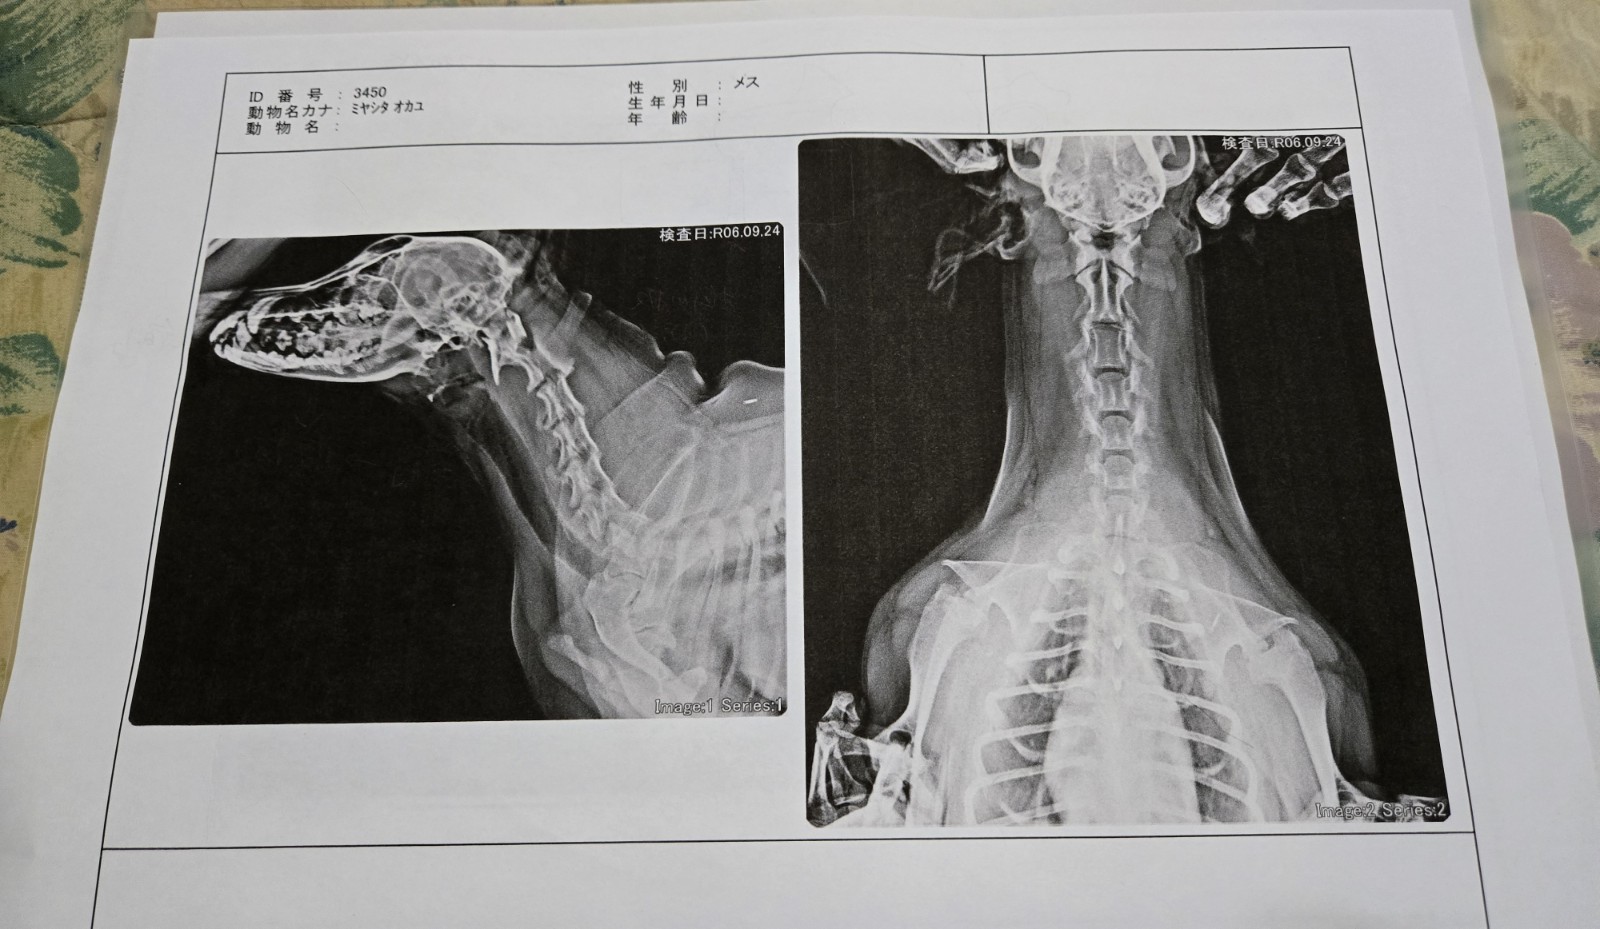

眼鏡犬。家に眼鏡があり、わんこと生活をしていれば1度くらいはやったことがあるはず。よく犬の視力は悪い・低い等、昔は言われていましたが現在は若干認識が違うそうで…確かに視力は人で言う所の0,2~0,3程度とやっぱり低い。車の免許に必要な視力が0,7なのでわんこは何らかの矯正が必要となる。また焦点を合わせるのも苦手らしく視界はぼやけているみたい。私が矯正してない視力が0,1位なのでなんとなくわかる気がしますが。ただ人よりも発達した嗅覚・聴覚で補っているので人よりもむしろ世界をよりはっきりとした形で捉えているみたい。漫画でよくありますね、視力を失ったが代わりにそれ以外の機能が発達して強キャラに登り詰めた人が…例えば、ufotable cafe 鬼滅の刃 キャラクター絵巻カフェ 柱合会議アクリルスタンド 悲鳴嶼行冥 単品 《ネコポス(ポスト投函)配送可》【中古】アニメ系トレカ/キャラクターグラフィティカード/カードダスマスターズ るろうに剣心-明治剣客浪漫譚- 第一幕 115:魚沼宇水とかかな?間違っても【新品】1週間以内発送 呪術廻戦 五条 悟 1/7 スケール フィギュア ごじょうさとる じゅじゅつかいせんこの人ではないな、目見えてるし。ちなみにこの子(かなで)は目が白くなり始めました。白内障か?と思い病院へ行った所目の老化との診断がされました。一安心。全てがこれと限りませんので気になったら都度、病院へ行く事をオススメします。最後に広告。YouTube『ふじむらなつきちch』にて動画を公開中。よろしければ見て頂き、チャンネル登録・高評価して頂けると励みになるのでおねがいします。